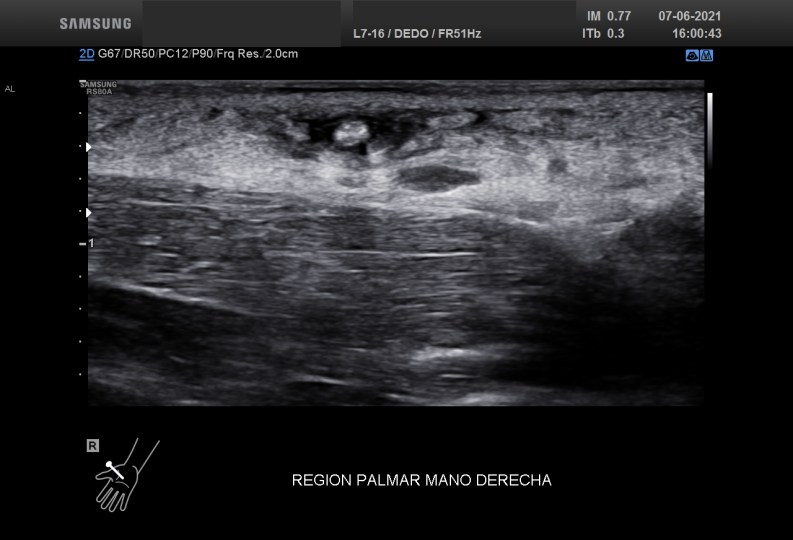

En el corte axial o eje corto que realicé sobre la zona afecta encontrémoslas rápidamente una estructura redondeada, hiperecogénica, al rededor de ella una pequeña cantidad de líquido y un engrosamiento importante del tejido circundante de lo que era claramente un cuerpo extraño.